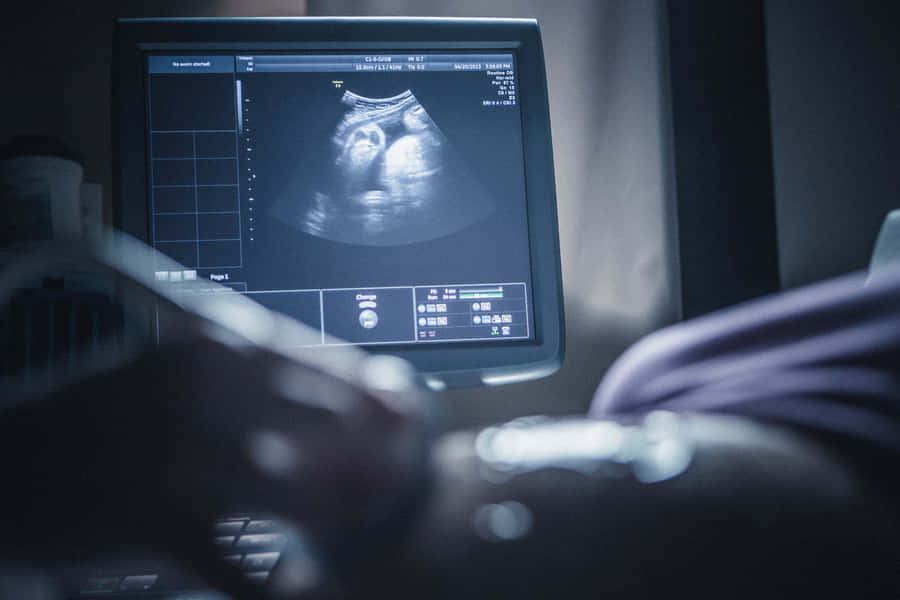

سونوگرافی بارداری، اطلاعات بسیار مهمی درباره جنین، سلامت آن و جنسیت آن به پزشک و مادران می دهد. سونوگرافی حاملگی در دوران بارداری اطلاعاتی درباره